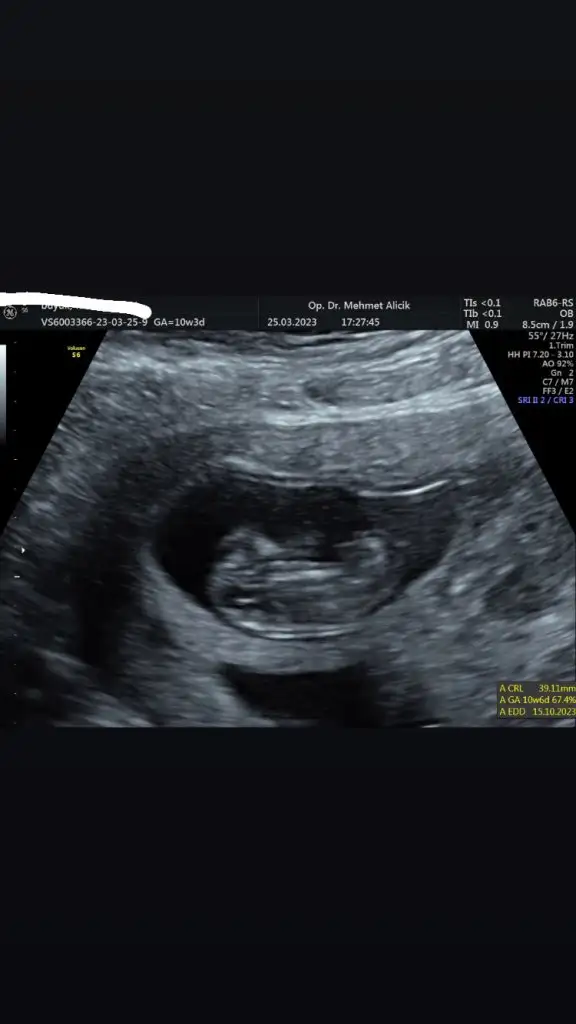

Merhaba 11+4 olduk bugün 🙏🏻 aranızda ultrason görüntüsünden cinsiyet anlayan var mı acaba ☺️ ultrasonda bakarken kafası böyle değildi daha yuvarlaktı ama bilemiyorum ben bakınca erkek diyorum ama içimden kız geçiyor 🥰

Papatyamaviss Papatyamaviss benim de mi belli olmaz.. ekledim en uygun foto bu 10.hafta bugüne ait